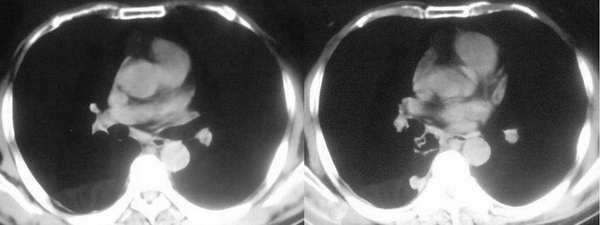

双肺胸膜下见大小不等圆形类圆形结节影,边缘较光滑;右肺下叶基底段靠隔顶及纵隔旁见团块状病灶,其内见偏心性厚壁空洞,洞内见短液平面,壁厚薄不均。纵隔淋巴结增大;右侧见少量胸腔积液。

右肺下叶基底段团块状病灶,其内见偏心性空洞,洞内未见液平面,可见壁结节;双肺野及双侧胸膜见多发大小不等软组织密度结节影,边缘较光滑,部分肺内结节有空洞形成;纵隔内见有重大淋巴结;右侧见少量胸腔积液。

两肺外周胸膜下可见多发大小不等的结节影,边缘稍模糊,可见细长毛刺,右肺下叶病灶部分融合成片团状,内出现多房空洞,部分内有小液平面,内壁较光整,壁厚不规则。气管前腔静脉后淋巴结肿大。考虑1韦格氏肉芽肿。2真菌感染(隐球菌)。其他待排。

气管前、腔静脉后可见肿大的淋巴结。韦氏肉芽肿为少见病例,发病率远低于肺癌